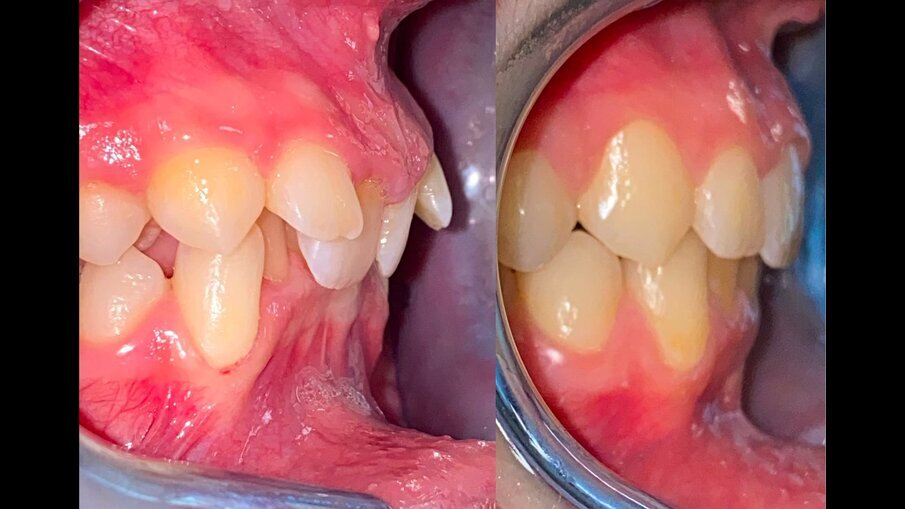

All’esame obiettivo intraorale si riscontra sul piano frontale un severo morso profondo con precontatto traumatico degli incisivi superiori contro la papilla retroincisiva e le rughe palatine anteriori durante la massima intercuspidazione, con overbite di 10 mm (Fig. 5). Dalle foto laterali si evidenzia una malocclusione di Classe II divisione 2 con scissor bite dell’elemento 1.5 (Figg. 6, 7), mentre dalle foto occlusali si rileva un grave affollamento con contrazione di entrambe le arcate maggiore nella zona premolare (Figg. 8, 9). L’analisi di Bolton mostra un eccesso superiore 3-3 di 2,34 mm (73,6%) e 6-6 di 2,76 mm (88,8%). L’analisi cefalometrica evidenzia una Classe II scheletrica, modello facciale normodivergente, angolo interincisale aumentato, incisivi superiori e inferiori retroinclinati (Fig. 10). La radiografia panoramica mostra la presenza dei germi dei terzi molari, assenza di parallelismo tra le radici dei premolari inferiori (Fig. 11) e una sovraeruzione degli incisivi inferiori che crea un doppio piano tra gli incisivi e i molari, segno di una curva di Spee molto profonda.

Fig. 6_Laterale destra pre-trattamento.

Fig. 7_Laterale sinistra pre-trattamento.